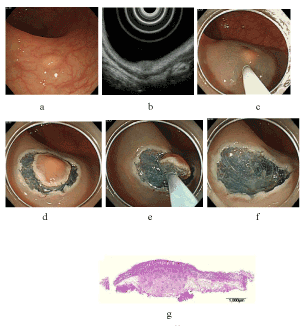

| Figure 1: Endoscopic mucosal resection after circumferential mucosal

incision (C-EMR). (a) A 6-mm-diameter carcinoid tumor in the lower rectum. (b) Thinning of the third layer corresponding to the submucosal layer by endoscopic ultrasonography. (c) Submucosal injection with hyaluronic acid. (d) Circumferential mucosal incision with a needle knife. (e) Snaring with a 27-mm oval snare. (f) After resection. (g) Histopathologically, the vertical distance of the resection margin was relatively sufficient from the lower edge of the tumor. |